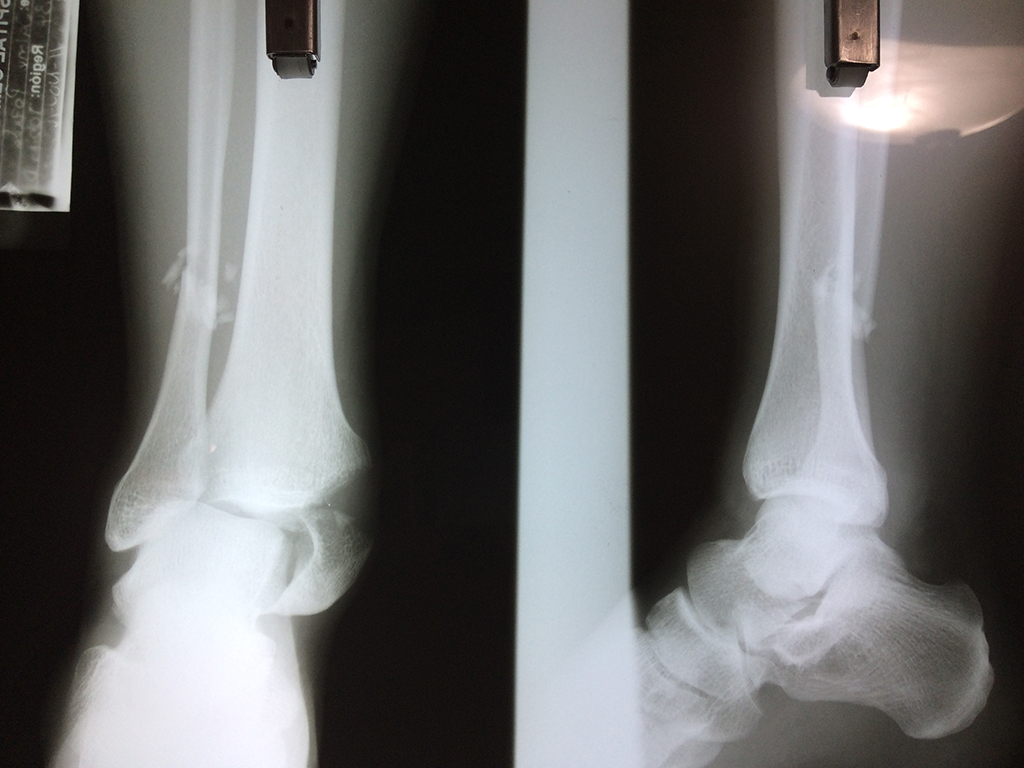

Una fractura de tobillo es la rotura de uno o más de los huesos del tobillo. Estas fracturas pueden ser:

- Parciales (el hueso está sólo parcialmente fisurado, no del todo).

- Completas (el hueso está perforado y está en 2 partes).

- Producirse en uno o ambos lados del tobillo.

Algunas fracturas de tobillo pueden requerir cirugía si: